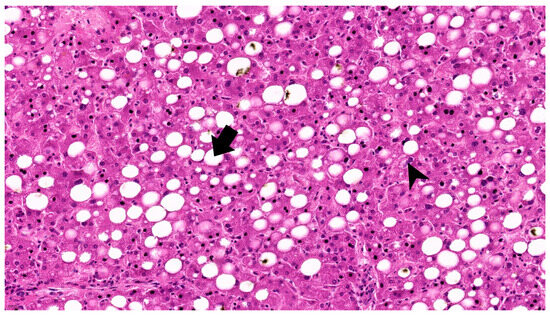

CT-derived entropy values corresponded closely with the severity of microscopic liver injury. The case with the highest first-order (1.86) and GLCM entropy (3.51), also presenting elevated transaminases (AST 60, ALT 66), showed severe histologic alterations, including both macrovesicular and microvesicular steatosis, sinusoidal congestion, and a high number of bi- and trinucleated hepatocytes (Figure 2).

Figure 2. Case 1 Hematoxylin-Eosin (424×): Severe macro and microvesicular steatosis (arrow) with numerous bi or trinucleated hepatocytes (arrowhead).